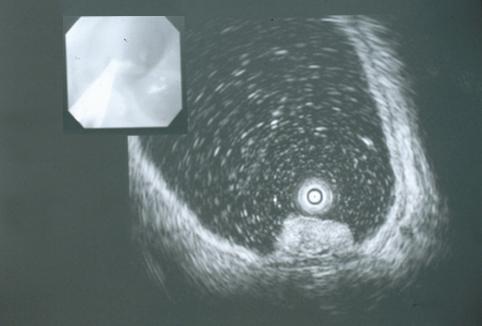

Criteria of Hist.ClassificationMalignant epithelial tumor/Adenocarcinoma

LocationStomach/Antrum

Technique, MethodUltrasonography

Macroscopic TypesType 0/I (I) Protruded type

Size15 - 19

Depth of Tumor Invasionmucosa